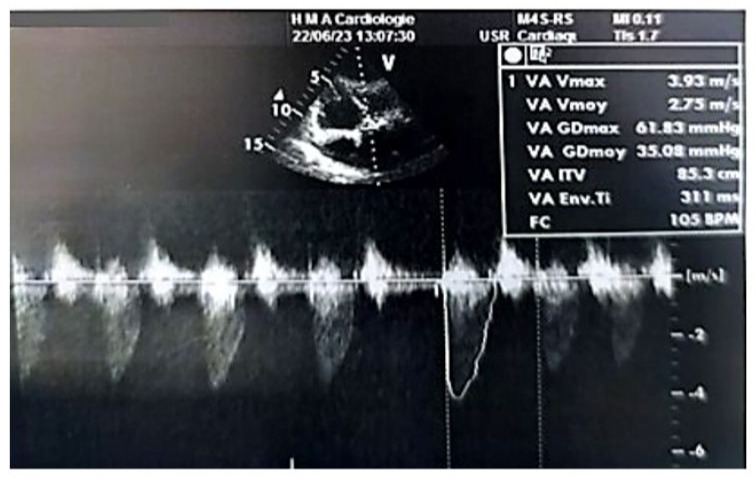

Left ventricular filling pressures were normal, and the inferior vena cava was dilated to 16 mm and slightly compliant. (Figure 3,4) The left atrium was dilated, with a surface area of 21.5 cm² and a volume of 44 ml/m². (Figure 5) The right ventricle had preserved systolic function with a TAPSE (Tricuspid Annular Plane Systolic Excursion) of 22 mm and a tissue Doppler S’ velocity of 12 cm/s. The right atrium was dilated at 19.7 cm², free of echoes. Assessment of the valvular apparatus showed a tricuspid aortic valve with degenerative changes, including calcified masses between the right and left cusps, limiting valve opening. Severe stenosis was noted, with a valvular area of 0.8 cm² (indexed area of 0.58 cm²), a Vmax of 3.93 m/s, and a mean gradient of 35 mmHg. The aortic annulus measured 19 mm, and minimal regurgitation was observed. (Figure 6-9)

Figure 7: Doppler echocardiographic image in the 5-chamber view at the level of the aortic valve, showing a mean transvalvular gradient of 35 mmHg.